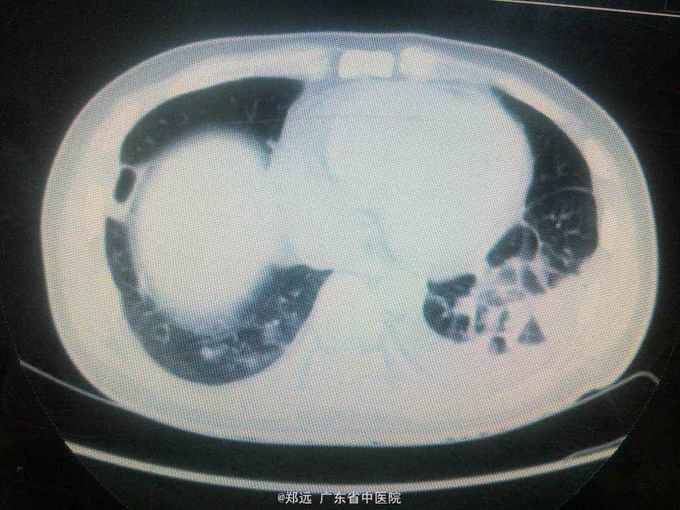

体查:双下肺湿啰音。三尖瓣区3/6级收缩期杂音。 胸部ct:双肺斑片结节影并空洞形成,左胸少量积液。血色素88克/升,白细胞11.48,中性粒81.3%,降钙素原14.84,ALT 121,AST 134.超声提示三尖瓣赘生物,三尖瓣大量返流。血培养金葡菌。

诊断:急性感染性心内膜炎,脓毒症,肺脓肿,丙型肝炎。 治疗:入院予万古霉素0.5克q6h,经治疗五日血象正常,降钙素原1.54,但仍反复高热,考虑肺脓肿合并阴性菌感染,加用头孢哌酮舒巴坦3克q12h,治疗五日仍有发热,血培养阴性,白细胞正常,降钙素原0.15,头孢哌酮舒巴坦改为美罗培南0.5克q8h,两日后无再发热,维持该方案至治疗四周后改予万古霉素0.5克q8h加美罗培南0.5克q12h继续治疗两周,复查超声提示三尖瓣熬生物较入院时缩小约三分之一,多次血培养阴性,胸部ct提示肺部炎症明显吸收予出院。出院后患者仍间发热,出院后约七周再次返院,查白细胞13.88,中性粒65.9%,血色素正常,降钙素原0.55,血培养提示溶血葡萄球菌,胸部ct示双肺多发感染灶,较前吸收,胸腔积液已吸收。予原万古霉素加美罗培南方案治疗,两日后无发热,治疗三周后多次血培养阴性,胸部ct提示肺部感染基本吸收,行三尖瓣赘生物切除并三尖瓣修补术,术中见三尖瓣后瓣瓣叶破坏严重,赘生物大小约2*1厘米。术后恢复良好,维持万古霉素加美罗培南治疗一周后改予万古霉素0.5克q8h加阿米卡星0.4克q12h治疗两周,赘生物及多次血培养阴性予出院。